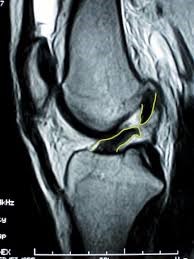

Μερικές εικόνες από μαγνητικές με ρήξη του προσθίου χιαστού συνδέσμου